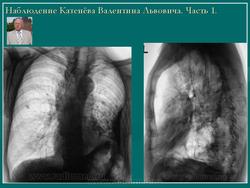

Обызвествления плевры